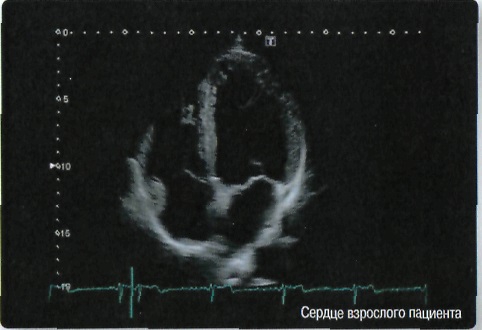

Кардиология:

Да

• TDI - тканевой доплер

• Стресс-эхо для исследований с фармакологической и физической нагрузкой и др.